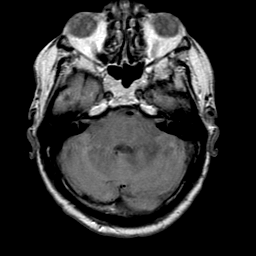

Meningioma, MR Study #1 -- Slice #4

[Home][Help][Clinical] Slice 4